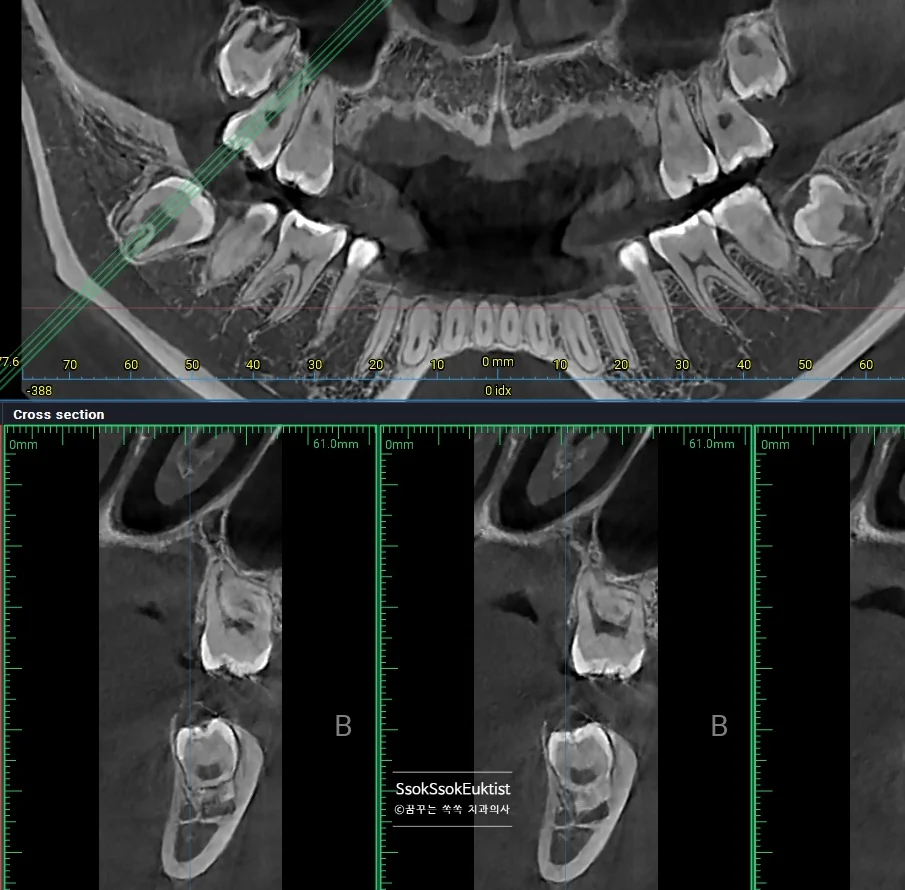

CBCT 3차원 영상 — 사랑니와 신경관의 인접 관계 확인

발치 전 CT를 보면 신경관과 맞닿아 있어 발치 난도가 높은 케이스임을 알 수 있습니다.

CBCT 3차원 영상 — 서로 다른 방향으로 휘어진 복잡한 뿌리

3차원 사진을 통해 보면 뿌리가 서로 다른 방향으로 휘어 있어 뼈를 잡고 있는 모습인데요^^ 이런 뿌리의 사랑니의 경우 한꺼번에 나오지 않으므로 머리를 분리하는 것 외에 뿌리도 분리하여 사랑니를 제거해야 합니다.

그렇기에 매우 어려운 발치 난도이며, 이러한 어려운 발치를 해낸다면 사랑니 발치를 잘하는 치과로 볼 수 있겠죠^^